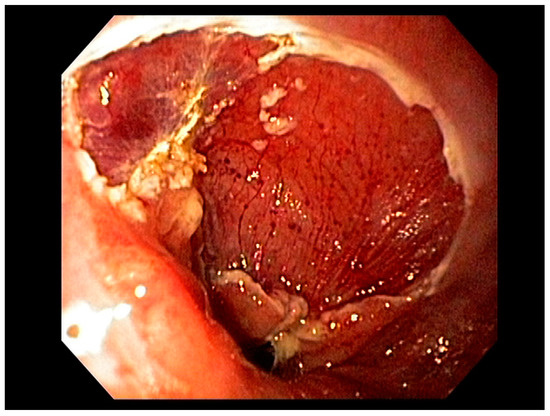

4.2. Early Gastric Cancer (EGC)

4.3. Endoscopic Ultrasound in Staging of Gastric Cancer